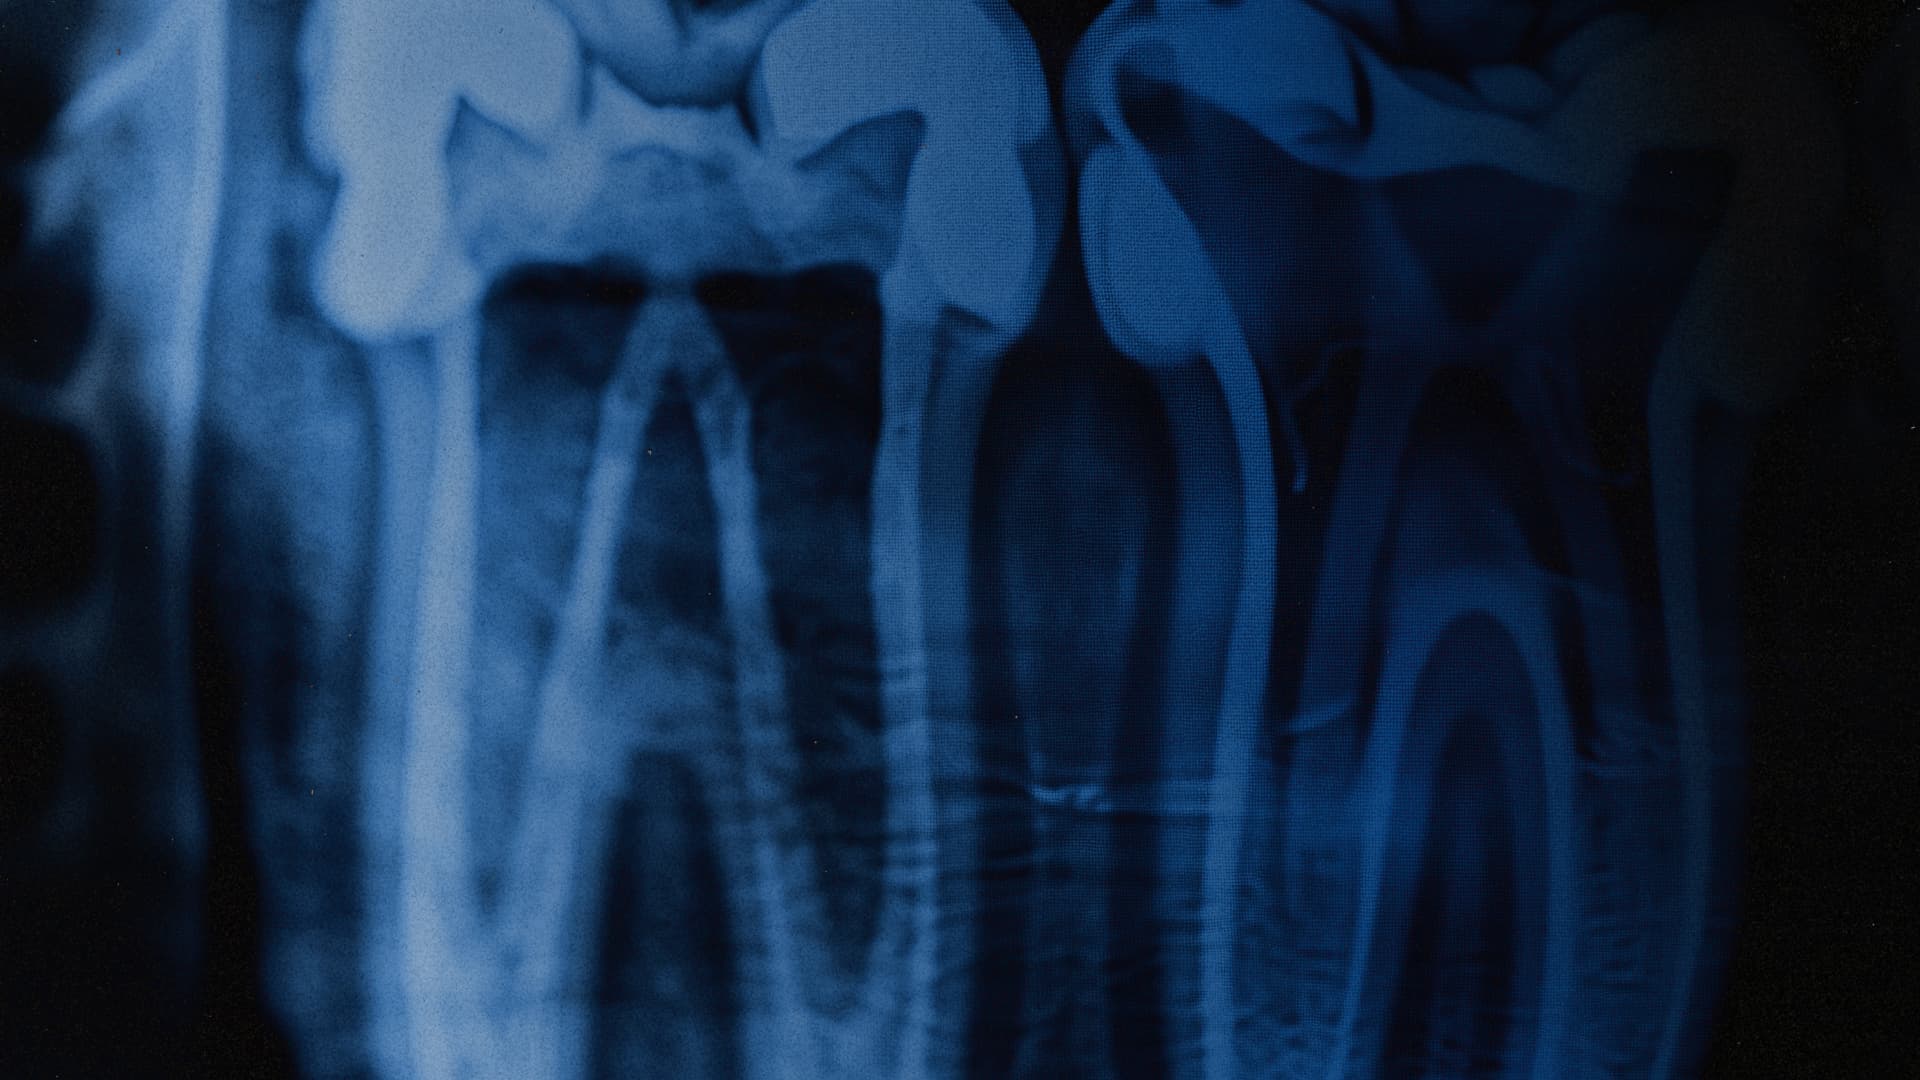

Проєкт Re:Smile бере на себе найскладніше: від пошуку спеціалістів, які допоможуть з імплантацією та протезуванням будь-якої складності, до супроводу на кожному етапі — від першого знімка до моменту, коли воїн знову зможе впевнено посміхнутися світу та дивитися в очі співрозмовнику.

● Протезування та імплантації, які повертають базову функцію жування та зберігають щелепну кістку.